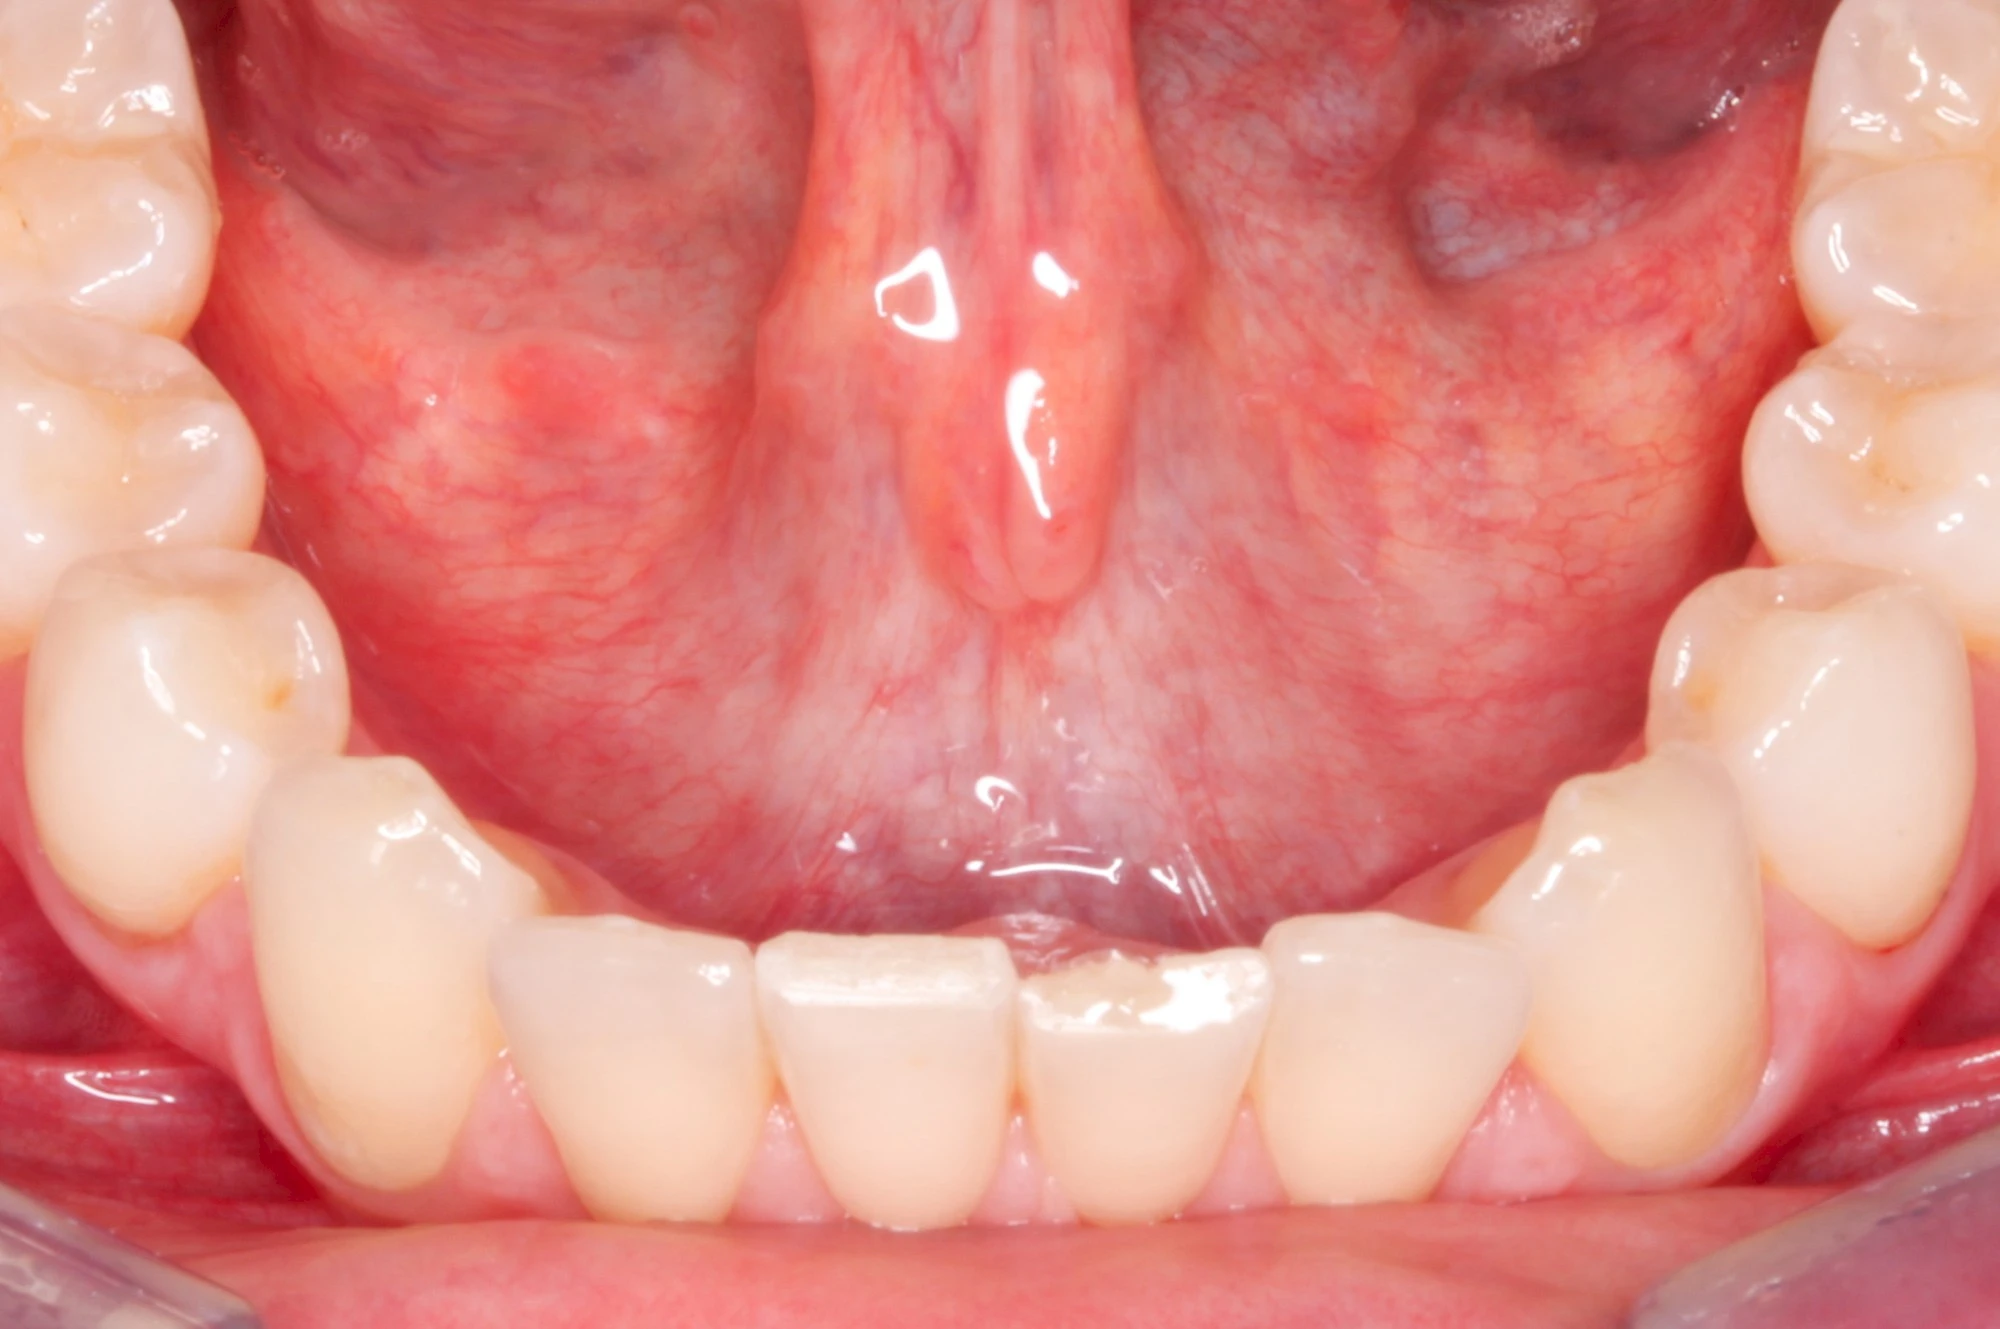

Schleimhäute

Schleimhäute kleiden Körperhöhlen aus – auch den gesamten Verdauungstrakt, beginnend mit dem Mund. Schleimhäute sind im Vergleich zur äußeren Haut viel dünner und weniger widerstandfähig. Der Aufbau ermöglich andererseits hochelastische Bewegungen. Lediglich die Zungenoberfläche, das Zahnfleisch und der Bereich des harten Gaumens ist etwas verstärkt (verhornt), da diese mechanisch z. B. beim Essen stärker beansprucht werden.

Die oberste Hautschicht der Schleimhaut wird Mukosa genannt (mucus – Schleim). Der Name leitet sich ab durch die Vielzahl an Speicheldrüsen (siehe unten), die direkt unter der Oberfläche liegen und mit Speichel und Schleimstoffen die Oberfläche angenehm elastisch, feucht und gleitfähig halten.

Im Vergleich zur äußeren Haut fehlen Haare, Talgdrüsen und Farbstoffe (Pigmente). Die rötliche Färbung ergibt sich aus der guten Durchblutung.

Speicheldrüsen

Es gibt insgesamt 6 große Speicheldrüsen (je 3 auf jeder Seite)

- Ohrspeicheldrüse (Glandula Parotidea – "Parotis")

- Unterkieferspeicheldrüse (Glandula Submandibularis)

- Unterzungenspeicheldrüse (Glandula Sublingualis)

Während die Ohrspeicheldrüse überwiegend dünnflüssigen Speichel vor allem zu den Mahlzeiten über einen kleinen Ausgang im Bereich der Wange etwa gegenüber den großen Backenzähnen (Molaren) absondert, ist der Speichel der Unterkiefer- und Unterzungenspeicheldrüsen eher dickflüssig und wird überwiegend unstimuliert – also zwischen den Mahlzeiten – über die sogenannten Carunceln unter der Zunge, abgesondert.

Daneben gibt es eine Vielzahl (600-1.000) kleiner Speicheldrüsen in den Schleimhäuten, die dazu dienen, die Schleimhäute ständig feucht zu halten.